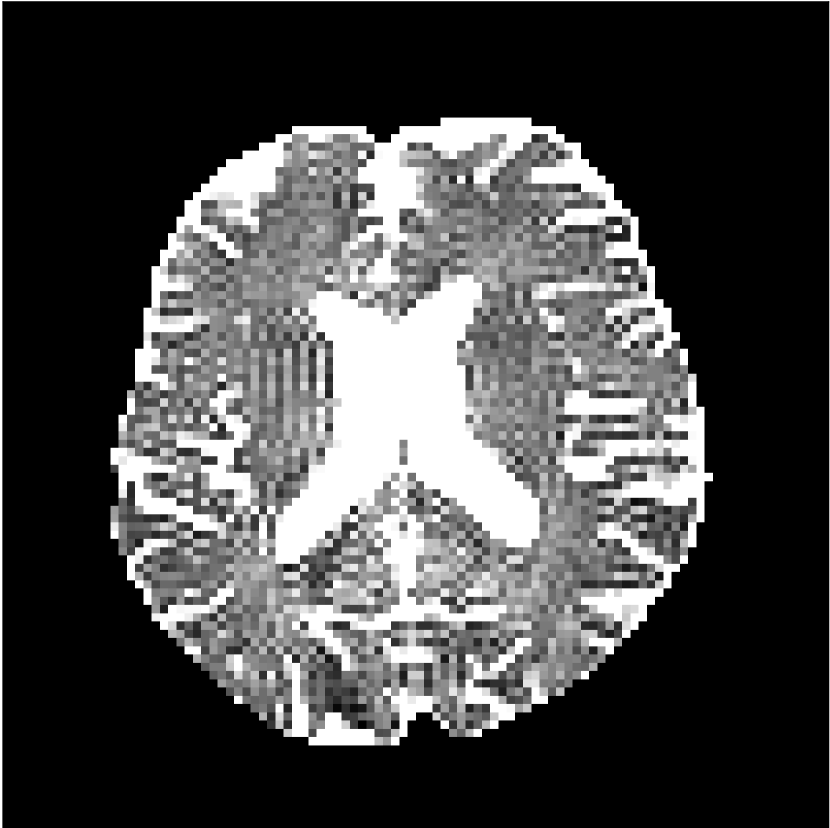

Figure 8 shows examples of non-diffusion-weighted images before and after processing. The raw images (Raw) served as the input for the magnitude deep learning (MCNN) and complex deep learning (CCNN) methods.

Raw

MCNN,

MCNN Resid.,

CCNN,

CCNN Resid.,

No PF

5/8 PF

Both methods remove artifacts, but the MCNN method allows residual rippling artifacts to pass through in the presence of partial Fourier. These rippling artifacts are not present in the CCNN method.